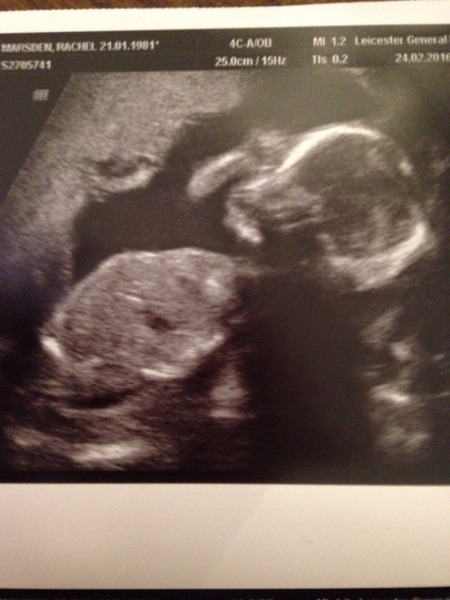

birdandbee · 23/02/2016 20:59

Congrats on the scans ladies 💙👶🏼💗👶🏻

cheery your pics are so cute!

Cheery1 lovely scan photo! Scase1firsttimemum glad the scan went well! Sorry to hear about the stuff with your mom.